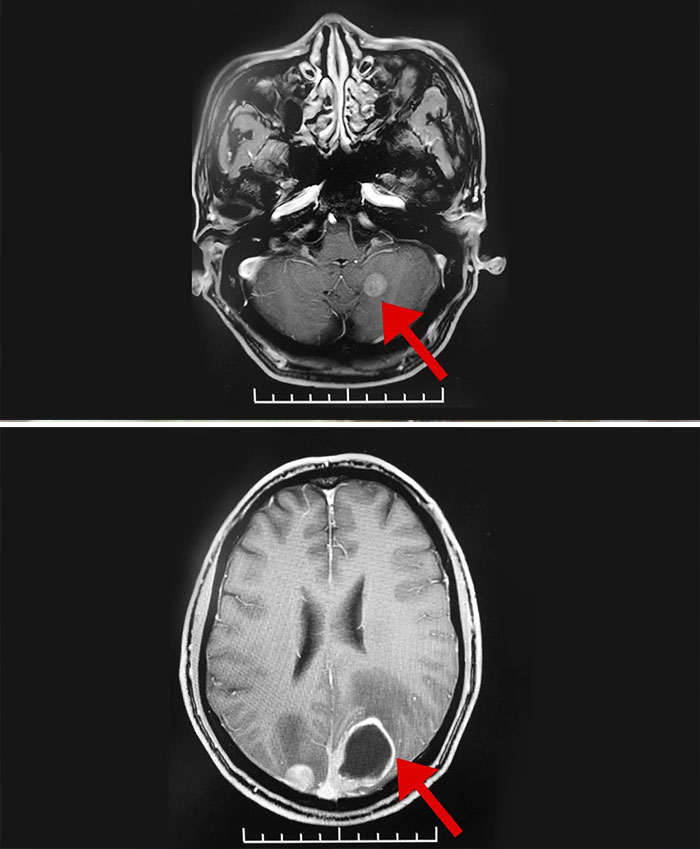

▲ 患者左侧小脑半球、双侧枕叶多发转移瘤

临床磁共振检查结果显示:李老伯左侧小脑半球、双侧枕叶多发转移瘤,中度高颅压,结合其已有头痛等症状,需尽快干预治疗。